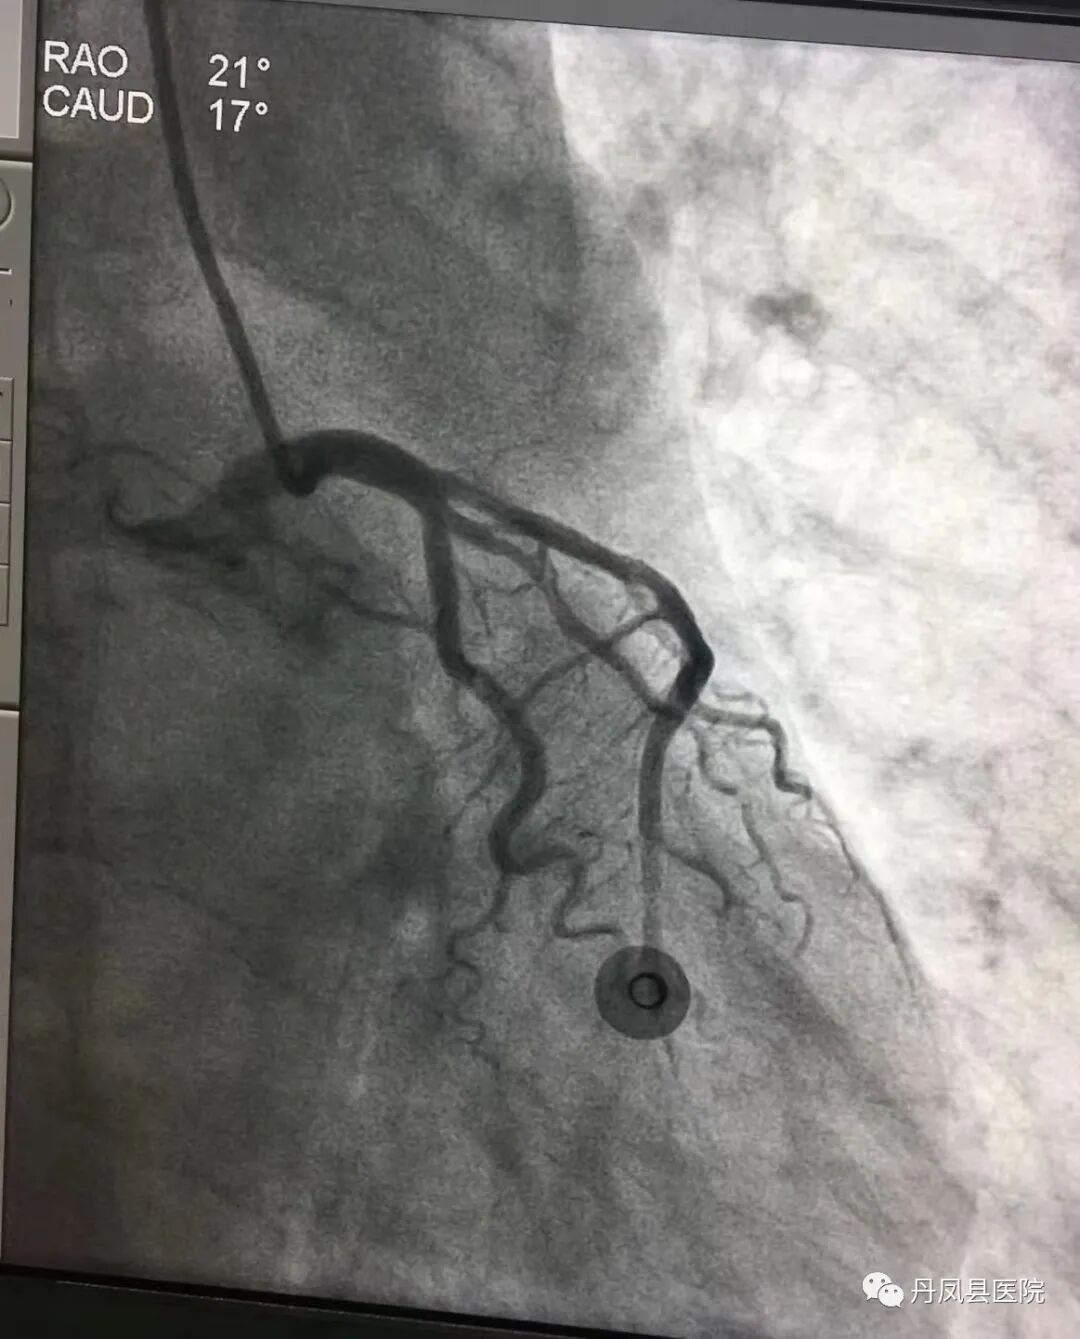

“准备除颤仪,立即口服心梗“一包药”,建立静脉通路,静脉注射普通肝素4200U!”刘大夫有条不紊的指挥,护士们迅速执行。9:20在经过患者家属知情同意并进行溶栓筛查后,胸痛中心医护人员给予患者注射用尿激酶原50mg静脉溶栓治疗,9:55溶栓结束。在心血管内科陈经鹏主治医师协助下,观察患者生命体征平稳后,联系商洛市中心医院胸痛中心,转运患者绕行急诊科,直达导管室。经造影证实患者属前降支病变,且血管再通,提示溶栓非常成功。

图为溶栓后冠脉造影图像